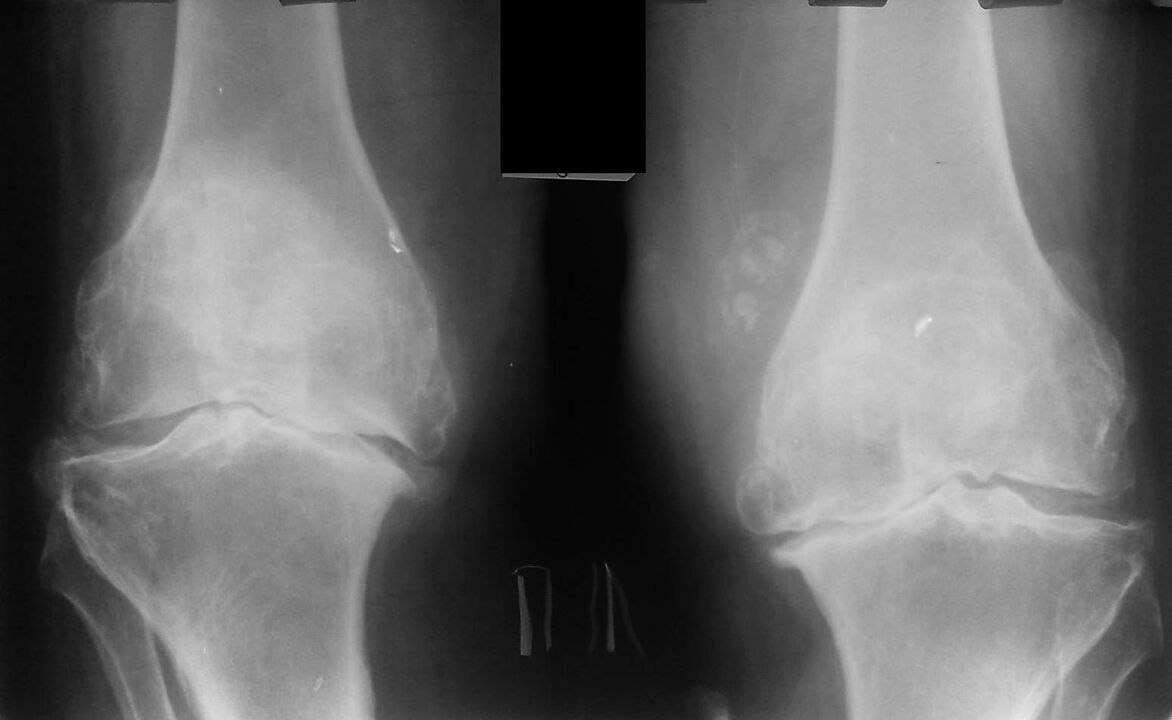

This diagnosis is made based on the patient's complaints, examination data, palpation of the diseased joint and X-ray examination.

Radiography is a standard research method that allows you to confirm the diagnosis, establish the degree of pathological changes, monitor the dynamics of the process, and also exclude other pathological processes (eg tumors) in the tibia and femur .

It should be noted that primary changes in knee joint structures on radiographs may be absent. Subsequently, joint space narrowing and subchondral zone compaction are determined. The joint ends of the femur and especially the tibia expand, the edges of the condyles become sharp.

Auxiliary diagnostic methods are CT (computed tomography) and MRI (magnetic resonance imaging), which allow a more detailed study of pathological changes in bone structures and identify changes in soft tissues.